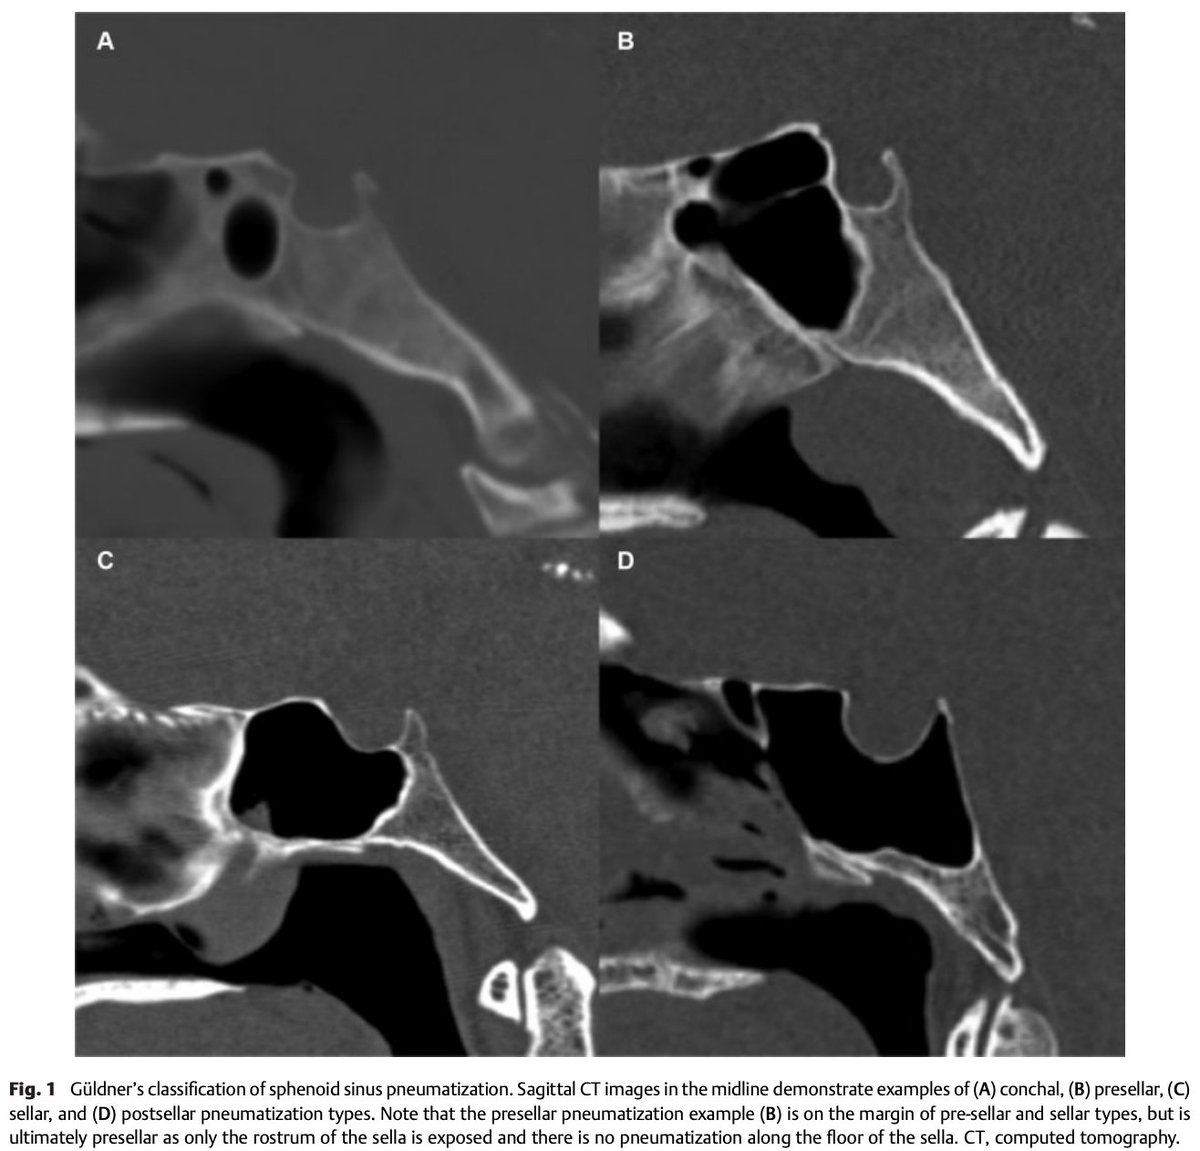

#JNLSB_Online Preoperative Computed Tomography Imaging of the Sphenoid Sinus: Striving Towards Safe Transsphenoidal Surgery#ENT#EEA#transsphenoidal#nsgy#safety#pituitary#approaches#neurorads#neuroanatomy https://www.thieme-connect.de/products/ejournals/html/10.1055/s-0039-1691831 … pic.twitter.com/c3kwPntykW